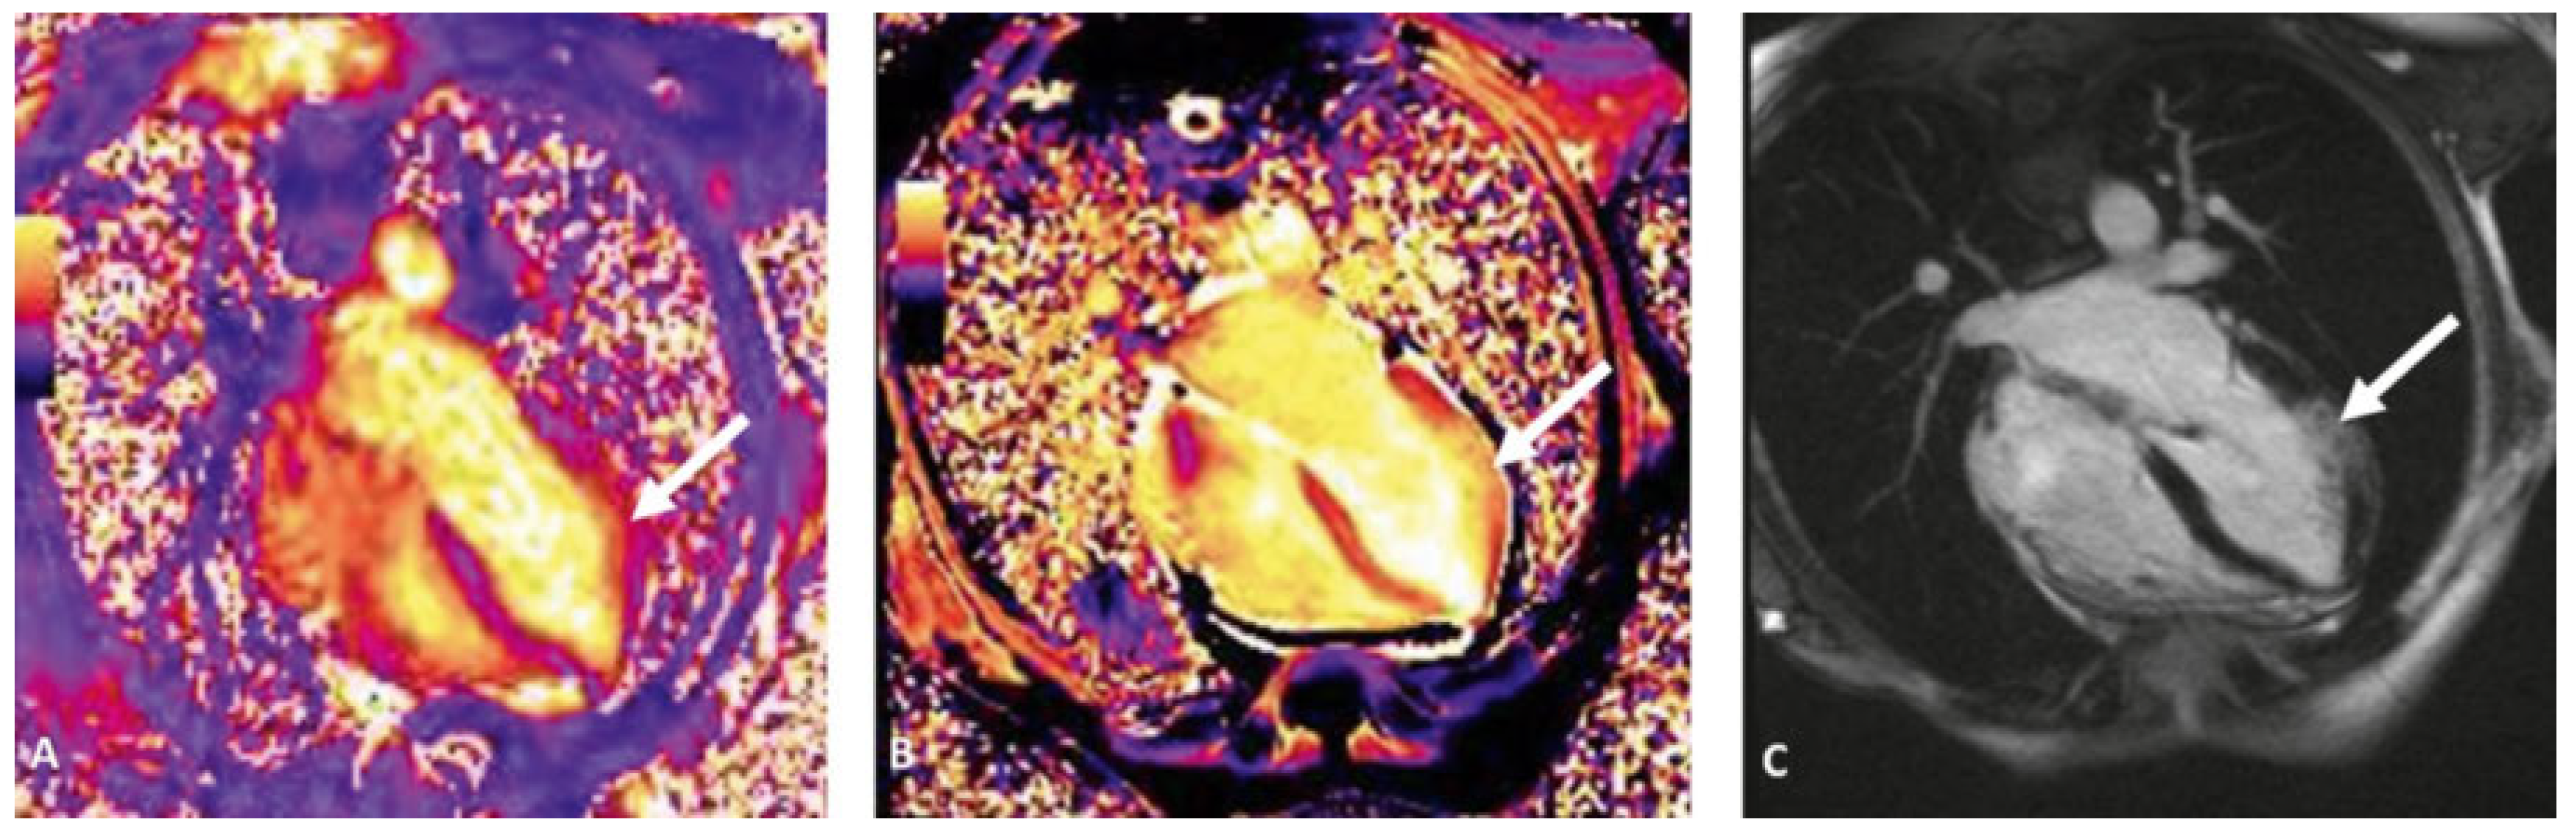

Case report